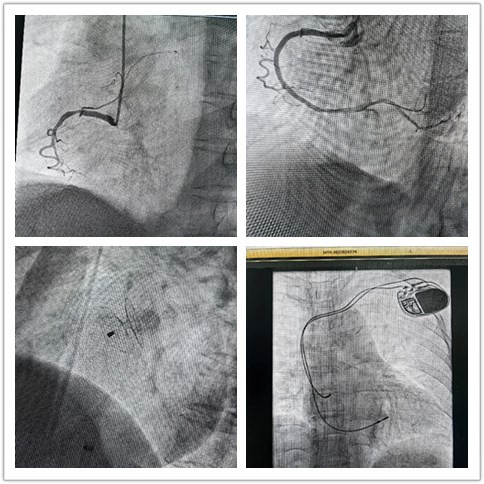

“组团式”帮扶队员—心内科邓纪钊,立即组织指导多学科团队开通胸痛绿色通道,有条不紊进行急诊术前相关检查,诊断为急性下壁心肌梗死。绕行病房,直达介入手术室,仅用32分钟顺利开通血管,患者转危为安,预后良好。

用“心”医治,点亮生命,是医者的初心使命。借力“组团式”帮扶,镇安县医院心内科救治能力和水平不断提高,业务范围不断扩展,先后完成多例卵圆孔未闭封堵、永久性心脏起搏器植入、心律失常射频消融术等。县医院从2022年3月组建介入科至今,截至发稿,冠脉介入手术已逾1000例,急诊冠脉内介入治疗手术已过百例,无1例手术相关医疗事件发生。这是镇安县医院发展史上的里程碑,也是前行的新起点。相信在六合彩网站